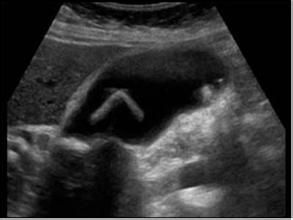

實驗室及輔助檢查:重點排除肝細胞性黃疸和溶血性黃疸。主要結合膽紅素升高;血清鹼性磷酸酶升高是膽汁淤積最具特徵的肝功能異常,通常首先出現;血清γ-谷氨醯轉肽酶在大多數膽汁淤積疾病均不同程度升高;慢性膽汁淤積患者血脂常顯著升高,主要是磷脂和總膽固醇。血清脂蛋白也增加,為低密度脂蛋白增加,高密度脂蛋白降低。有一種異常的脂蛋白X(屬於低密度脂蛋白)增高,具有鑑別意義。影像學檢查了解有否膽道梗阻及梗阻的具體病因。

判定是肝內還是肝外膽汁淤積,需根據超聲、CT、MRCP/ERCP/PTC/超聲內鏡等檢查。